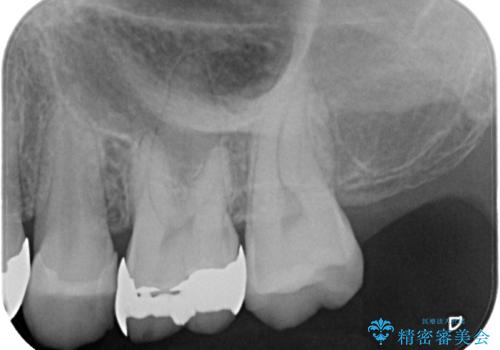

- 銀歯が取れたとのことで来院された患者様です。患者様の歯をあまり削りたくないというご希望に添い、セラミックインレーにて治療を行うこととなりました。

拡大鏡視野下で、保険のプラスチック、虫歯の除去を行い、セラミックインレーに適した形に整えました。

歯と歯茎の間に圧排糸と言われる糸を入れてシリコーン印象材にて精密な型どりをしました。